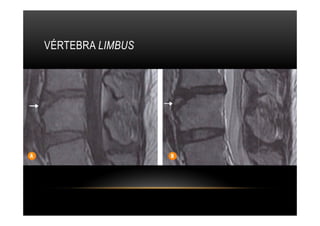

VÉRTEBRA LIMBUS